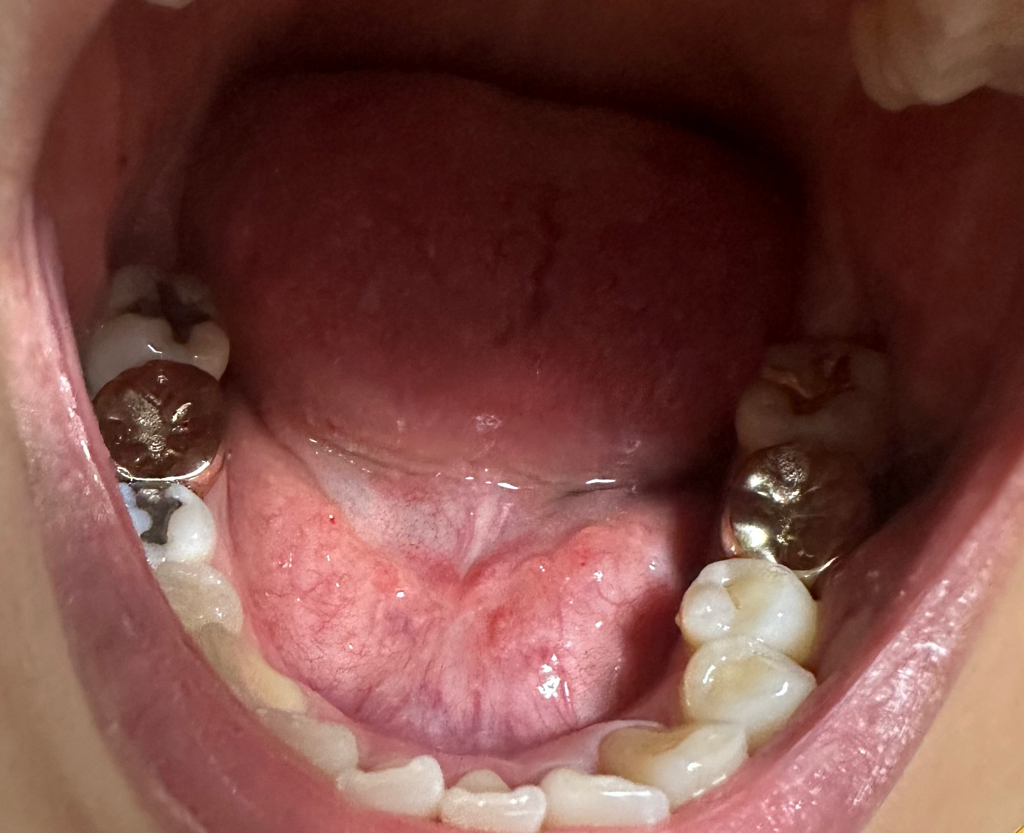

혀 밑이 좀 많이 튀어나와 있는 것 같은데 정상인가요?

어쩌다 혀 밑을 보니 살같은게 많이 튀어나와 있는 것 같은데 제 기준으로 왼쪽이 더 부풀어 있는 것 같아서요

작년부턴가 귀밑 턱밑쪽에 묵직한 느낌이 들었고

입안도 많이 건조한 편입니다

건강검진 수치에서도 아밀라제 수치가 180정도로 높게 나왔어서

혹시 이거 관련인가 해서 여쭤봅니다ㅜㅜ

정상적인 모양인지 한번 봐주시면 감사하겠습니다.

• 2번 째 사진